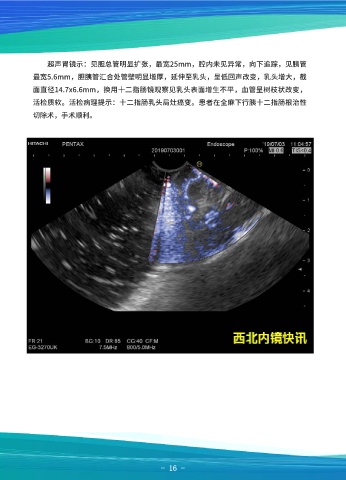

超声胃镜示:见胆总管明显扩张,最宽25mm,腔内未见异常,向下追踪,见胰管

最宽5.6mm,胆胰管汇合处管壁明显增厚,延伸至乳头,呈低回声改变,乳头增大,截

面直径14.7x6.6mm,换用十二指肠镜观察见乳头表面增生不平,血管呈树枝状改变,

活检质软。活检病理提示:十二指肠乳头局灶癌变。患者在全麻下行胰十二指肠根治性

切除术,手术顺利。